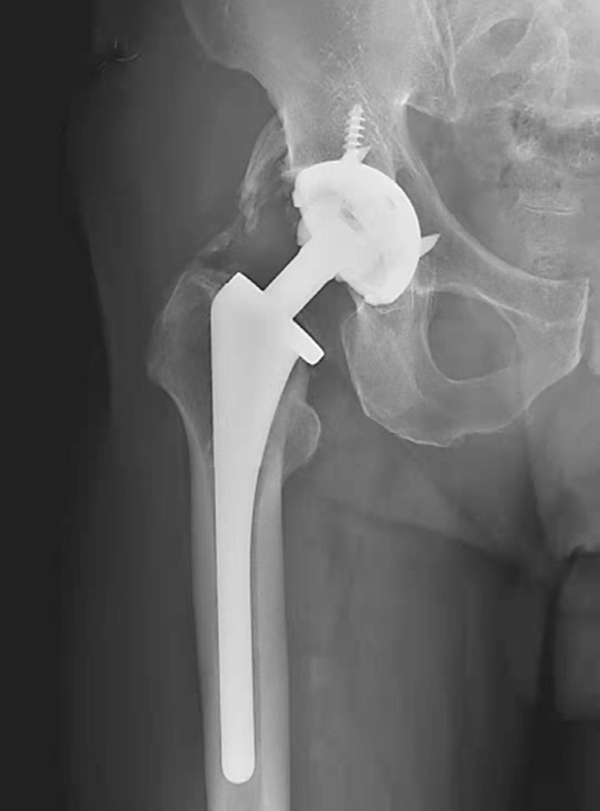

图4 右侧人工髋关节置换术后感染并松动

女性,89岁。发现右大腿中段后侧流脓2个月余。平片,示右股骨上段骨密度增高,内侧骨膜增生,假体周围骨质吸收,髋臼杯内陷,人工股骨柄部内移